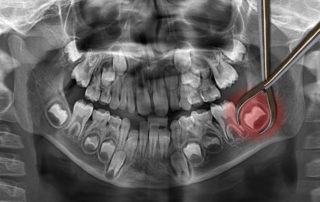

Wisdom Teeth Removal After 30: What Should You Know Many people go through a good chunk of their life hardly even knowing their wisdom teeth are there. They haven’t come through the gums (aka erupted) [...]

Wisdom Teeth Removal After 30: What Should You Know Many people go through a good chunk of their life hardly [...]